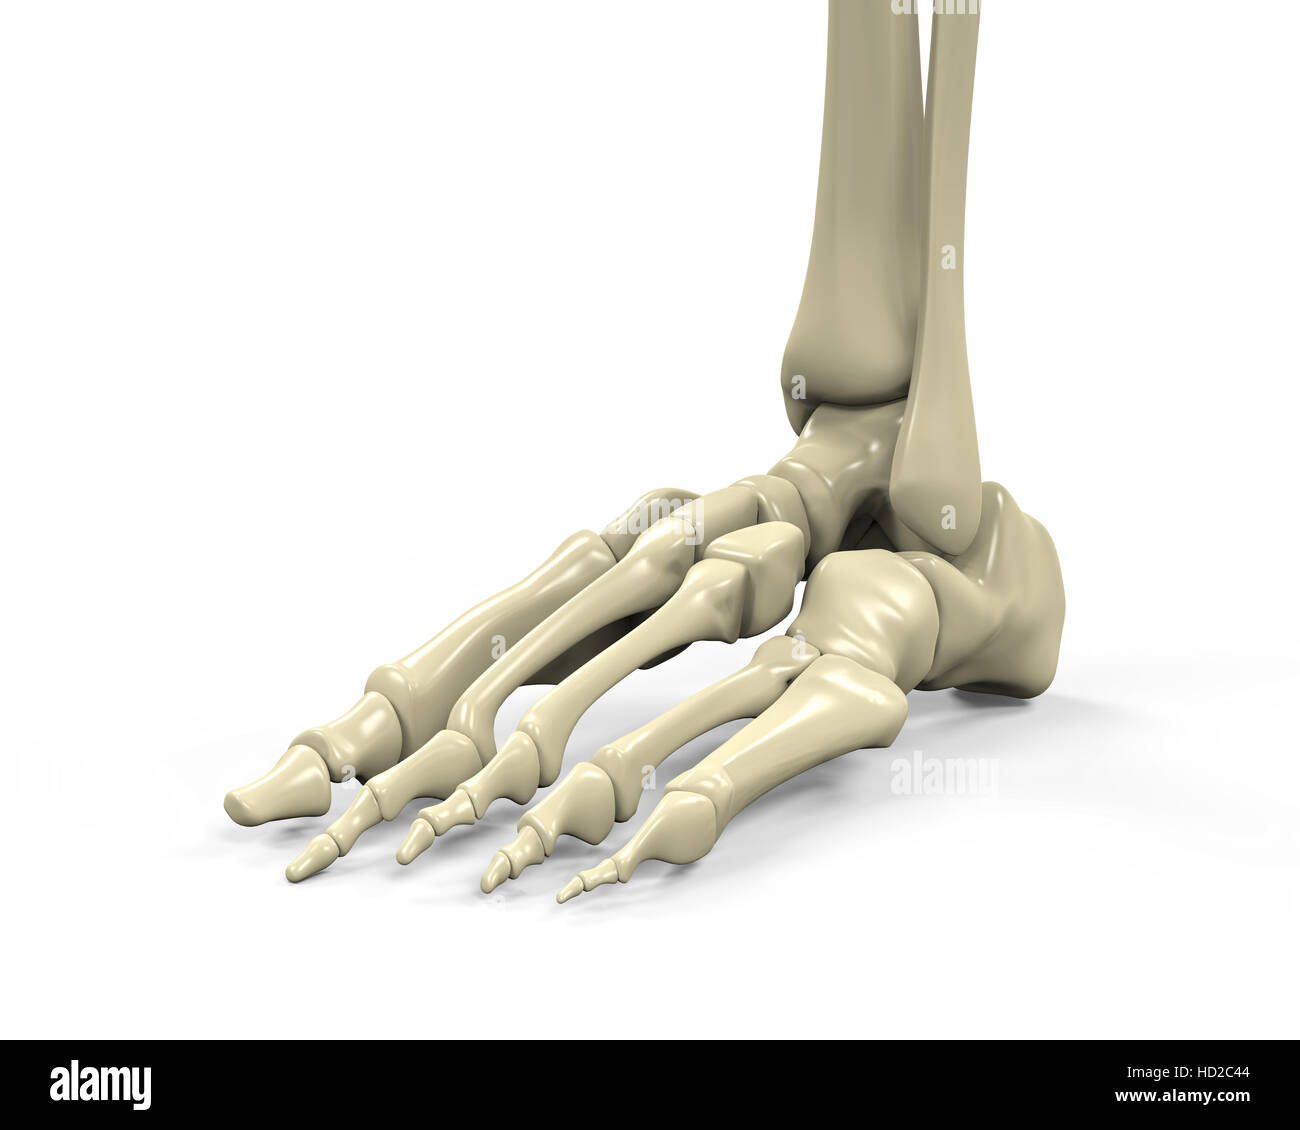

RF2GMNAX6–Vue latérale externe du squelette d'un pied humain articulé, avec la partie distale du tibia et du péroné montés sur un fil. Concept anatomique